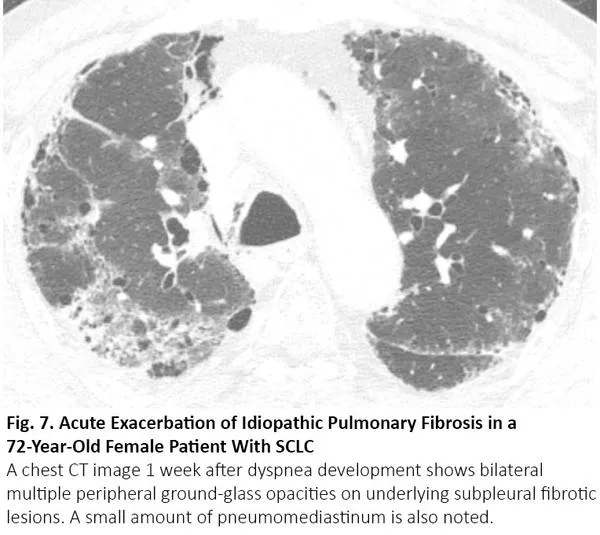

COVID-19患者的肺部CT的典型表现为双侧多发磨玻璃样影,好发于肺周3(图1)。61%~72%的COVID-19患者在症状出现后1周左右有典型CT表现,而非COVID-19患者只有不到10%人群有此类表现。4,5

图1. COVID-19患者胸部CT的典型表现